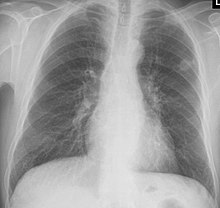

Je weicher die Strahlung (niedrige kV-Werte) ist, desto größer ist der Anteil der vom Gewebe absorbierten Strahlung. Dadurch werden auch feinste Gewebeunterschiede auf dem Röntgenfilm sichtbar gemacht. Dies ist der Fall bei der Mammografie (Röntgenuntersuchung der weiblichen Brust), jedoch ist die Strahlenbelastung des durchstrahlten Gewebes dadurch relativ hoch. Harte Strahlung (über 100 kV) durchdringt Gewebe und Materialien (Gips und sogar Bleischürzen von geringerer Dicke) wesentlich leichter. Kontrastunterschiede werden stark abgemildert, wie z. B. bei Lungenaufnahmen (120 kV), bei denen sonst im Bereich der Rippen keine Beurteilung der Lungenstruktur möglich wäre.